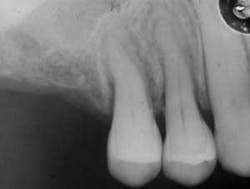

Radiograph of widened periodontal ligament space. Courtesy of Dr. T.D. Rees

Scleroderma may occasionally be associated with idiopathic resorption of teeth and bone. Periodontal ligament widening may be a part of the characteristics and noticeable on radiographs (see Figure 3). A loss of the attached gingiva and noted recession may be seen in some patients with CREST (see related article on “Forms of Scleroderma”).